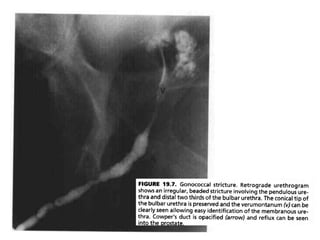

• The typical urethrographic finding in gonococcal urethral stricture is

an irregular urethral narrowing several centimeters long.

• While the bulbar urethra is the most common area of occurrence,

gonorrheal strictures may occur anywhere in the anterior urethra or

may even involve the entire anterior urethra

Gonococcal urethral stricture. Retrograde

urethrogram reveals a segment of irregular, beaded narrowing

in the distal bulbous urethra with opacification

of the left Cowper duct